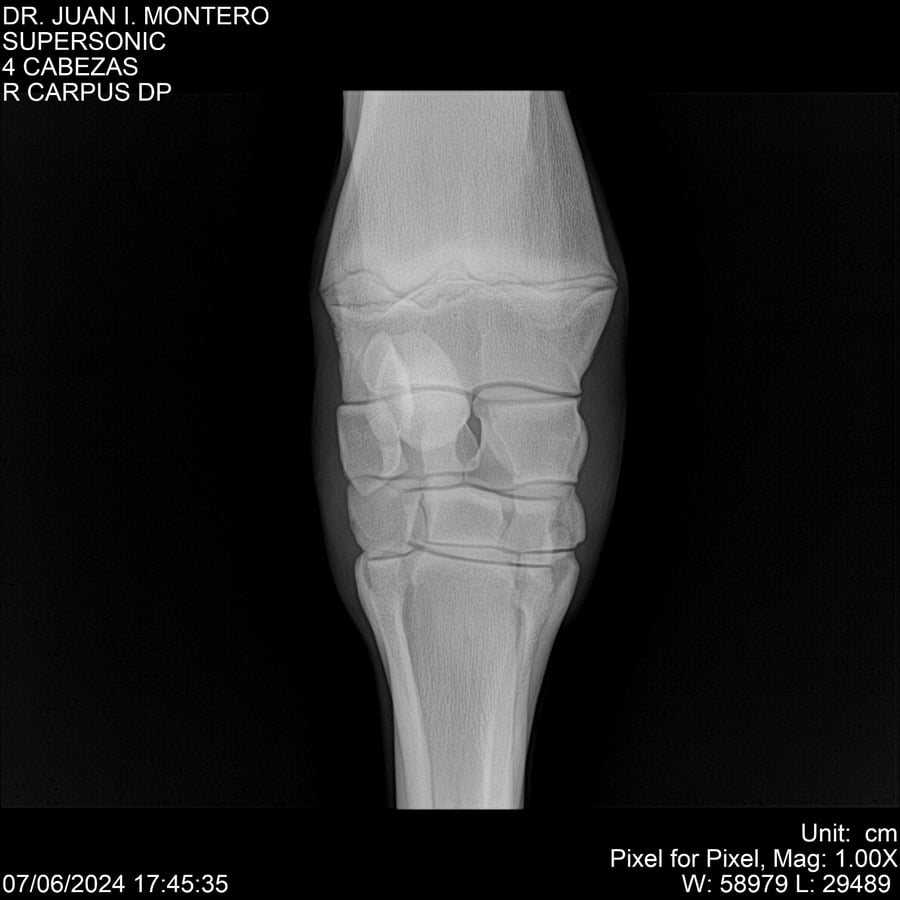

LOTE 5, SUPER SONIC Lote Anterior Volver al remate Lote Siguiente Ficha Contacto Montevideo - Ficha del Lote Identificador: #281089 Categoría: Yeguarizos Montevideo - 69 Visualizaciones ClicData Contacto Empresa: Abelenda N. R., Walter Hugo Nombre*: Teléfono* : E-mail* : Mensaje Enviar Registrese gratis Este contenido Exclusivo está disponible sólo para usuarios registrados Ingresar